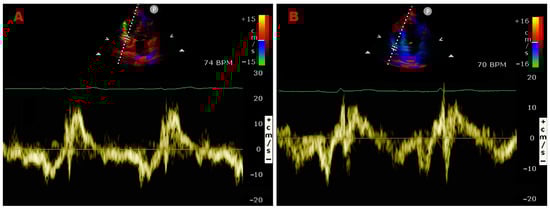

Figure 5 illustrates representative examples of PW-TDI assessment of RA pseudomasses.

Figure 5.

Examples of PW-TDI assessment of the systolic infolding of the lipomatous right atrioventricular junction (A) and of the RA infero-lateral wall (B). Spectral PW-TDI allows for the detection of a pattern of concordant motion in synchrony with the phases of the cardiac cycle, thus indicating RA pseudomasses. PW, pulsed wave; RA, right atrial; TDI, tissue Doppler imaging.